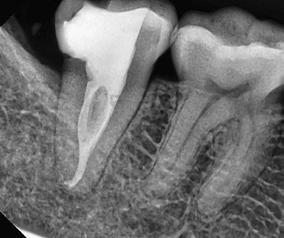

1. ábra: A 12. fog - a röntgenfelvételen nagyméretű periapikális elváltozás látható. A tünetmentes fogat ISO 25/.06 TF Adaptive reszelővel (Kerr Dental) preparáltuk. – 2. ábra: A 12. fog gyökércsatornájának tömését ásványi trioxid aggregátummal (ENDOSEAL MTA, Maruchi) végeztük. Figyeljük meg az apikális elágazás lezárását, ami az apikális terminus hatékony tisztítása és dekontaminálása miatt lehetséges. A gyógyulás 12 hónap elteltével csaknem teljes volt. – 3. ábra: 33. fog - a páciensnél egy bukkális sinus traktus volt látható, amely röntgenfelvételen a 32. és a 33. fog közötti területnek felelt meg. A CBCT és a röntgenfelvétel nagyméretű periradikuláris elváltozást mutatott, különösen a disztális oldalon. A preparálást 20/,07v ProTaper Gold (F1; Dentsply Sirona) készülékkel végeztük. – 4. ábra: A 33. fog gyökércsatorna obturációját sealer és hordozó alapú guttapercha (AH Plus és Thermafil, Dentsply Sirona) segítségével végeztük. A hat hónappal a műtét után végzett röntgenellenőrzés azt mutatta, hogy több oldalsó csatorna feltöltődött, és a gyógyulási folyamat folyamatban van.

keletkeznek [25-29]. A másodlagos kavitációs buborékok összeomlásuk során a csatornafalak közvetlen közelében vannak, nyírófeszültséget és örvényes áramlásokat generálva, amelyek képesek eltávolítani a törmeléket, a kenetréteget és a biofilmet a gyökércsatorna felszínéről, valamint a fel nem fedezett és műszerrel nem rendelkező anatómiai területekről, például az isztmuszokból, az oldalsó csatornákból, a hurkokból és a ramifikációkból, ezáltal tovább fokozva a tisztítási és dekontaminációs mechanizmust (1-4. ábra). A gyökércsatorna mentén létrejövő fokozott nyomás következésképpen az irrigálószereknek a dentinális tubulusokba való behatolásának mélységét is növeli [25-28].